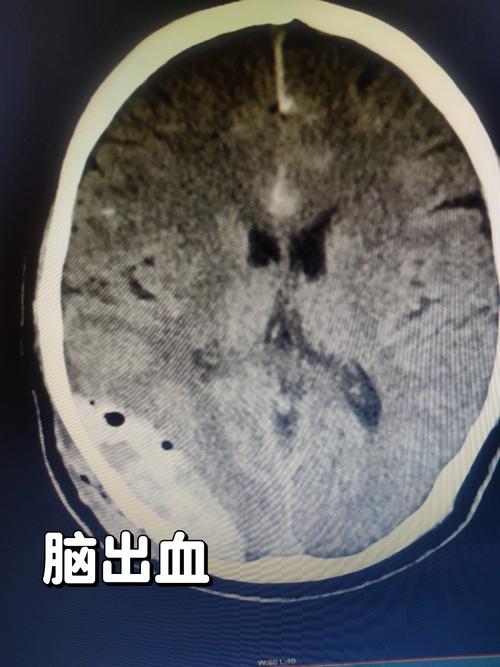

(图片来源网络,侵删)

(图片来源网络,侵删)- 糖尿病、高脂血症:会加速全身血管的动脉粥样硬化,包括脑小血管。